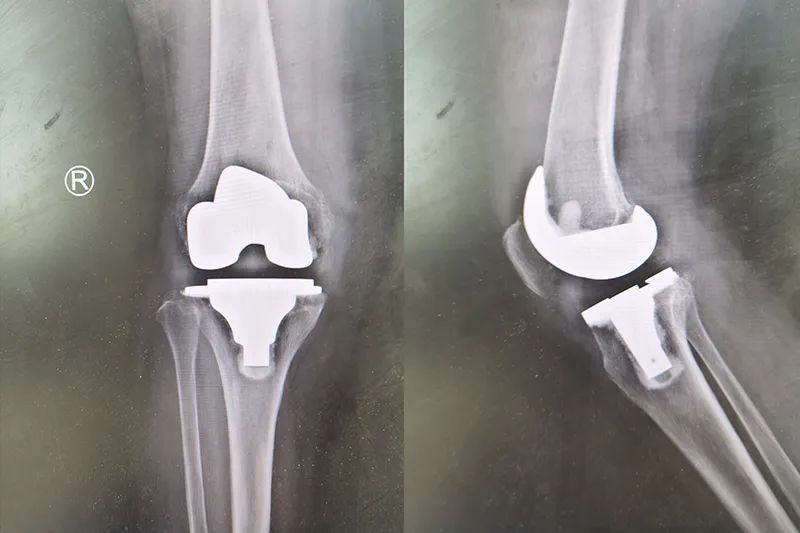

1、髋、膝、肩等四肢关节各种关节炎(骨性关节炎、创伤性关节炎、强直性关节炎、感染性关节炎等)、股骨头无菌性坏死、关节畸形等;每年开展髋、膝关节置换、翻修、肩关节置换、关节矫形、关节松解融合等四肢关节手术500多例;

5、骨科加速康复外科,引进 ERAS 快速康复理念,降低手术并发症,缩短患者治疗时间,加速患者康复,大大提高了治愈率;科室拥有CPM机6台,气压治疗设备7部等相关设备辅助患者术后康复。

主任医师、安徽理工大学兼职教授、亳州市医学会骨科学会主任委员、亳州市首届学科及技术带头人、中国骨质疾病专业委员会常委、安徽省医学会骨科学会常委、安徽省医师协会骨科学分会委员、安徽省微创学会骨科学会常委、安徽省创伤学会委员、安徽省骨科学会关节学组委员、安徽省骨科学ERAS骨质疏松学组委员、安徽省骨科专业质量控制中心委员、亳州市劳动能力鉴定专家、亳州市东生司法鉴定所专家。享受市政府特殊津贴,曾在德国、美国、香港进修学习关节手术,参与或主持多项新技术并获奖。在治疗股骨头无菌性坏死、髋臼发育不良、强直性脊柱炎、风湿和类风湿关节炎、膝关节骨性关节炎、髋部骨折、微创接骨方面有很深的造诣。

主治医师,毕业于江西省赣南医学院临床医学系,安徽医师协会手外科医师分会再植再造工作委员,擅长对骨科疾病的诊断和治疗,能熟练完成股骨头无菌坏死,膝关节骨性关节炎,风湿性关节炎等诊断及手术治疗(人工股骨头,人工全髋关节,膝关节,肩关节置换),四肢骨折手法复位及手术治疗。